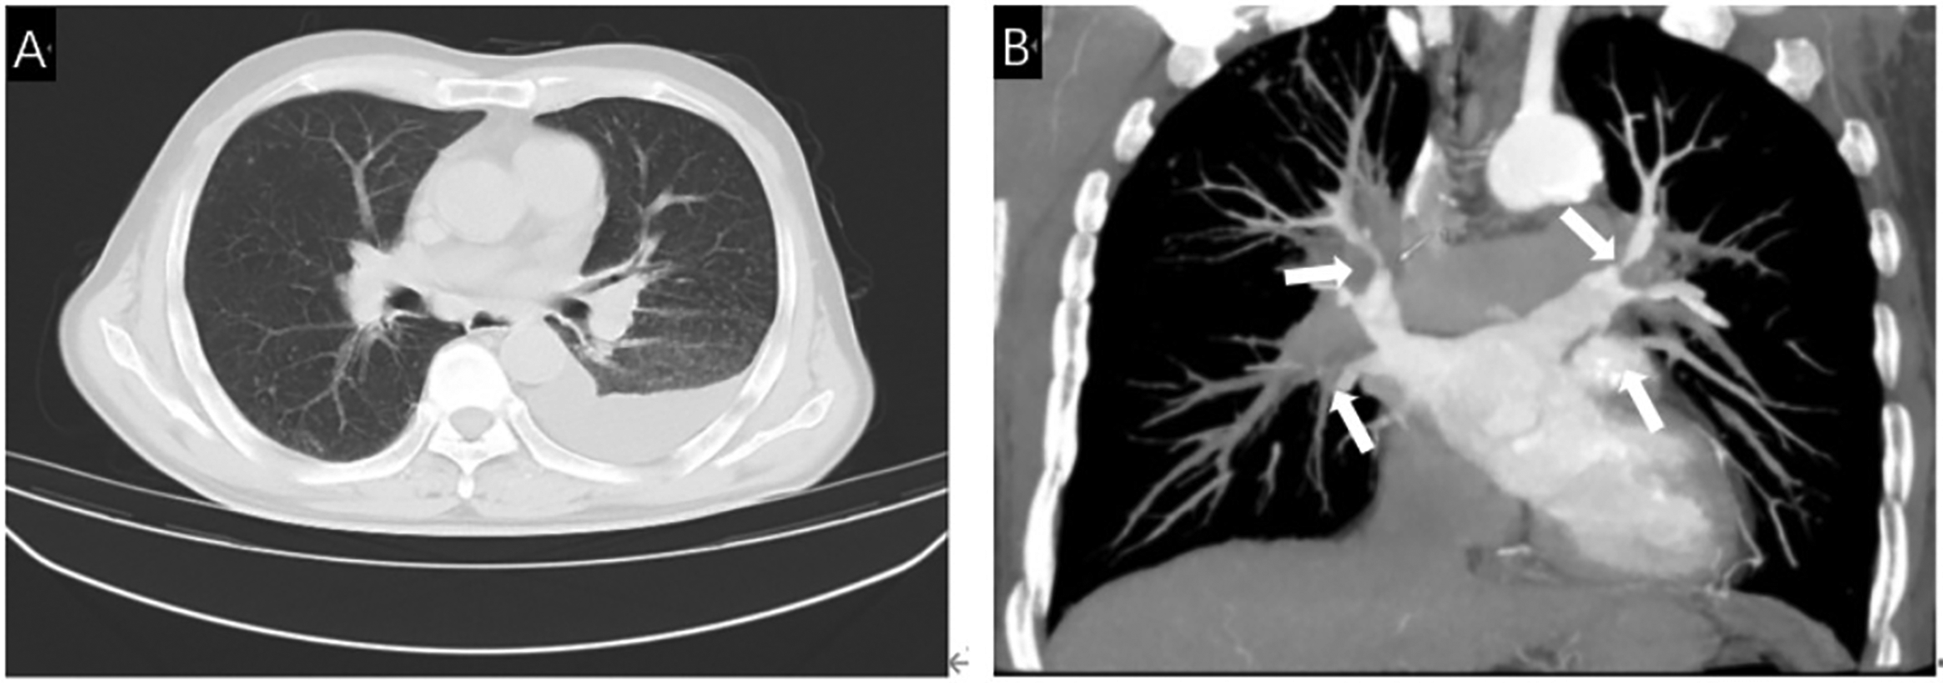

A 66-year-old male was admitted to the Second Hospital of Lanzhou University due to chest tightness and shortness of breath with cough. The patient had a history of tuberculosis, 15 years of underground mine work, and occupational exposure to pneumoconiosis. Laboratory tests after admission revealed that the number of neutrophils was 6.59 × 10 × 9/L, the percentage of neutrophils was 0.70, the C-reactive protein level was 26.12 mg/L, the erythrocyte sedimentation rate was 20.0 mm/h, the N-terminal atrial natriuretic peptide level was 75.74 pg/ml, and the pleural effusion sent for testing revealed fluid leakage. There were no obvious abnormalities in coagulation function, liver or kidney function indices, electrolytes, tuberculosis-related examinations, or infectious disease indicators. Cardiac ultrasound revealed that the left ventricle had normal systolic function, mildly decreased diastolic function, a pulmonary artery systolic blood pressure of 55 mmHg, and moderate tricuspid regurgitation. Chest CT without scan imaging revealed multiple nodules and calcifications in both lungs, multiple old lymph nodes in both the hilum and mediastinum, left pleural effusion, and tuberculosis. Contrast-enhanced CT of the pulmonary vein revealed severe pulmonary vein stenosis in both the upper and left lower lobes, and FM was more likely to be considered, as shown in Figure 1.

(A) Chest CT showed multiple lymph nodes in both hilar areas and left pleural effusion. (B) Contrast-enhanced CT showed severe stenosis due to compression of bilateral pulmonary veins by fibrous tissue (White arrow).